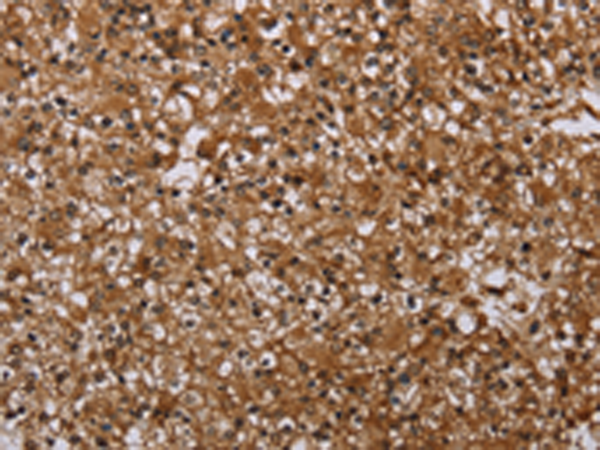

分类: 科研抗体货号: P05126别名: P2X3应用: WB,IHC反应种属: Human